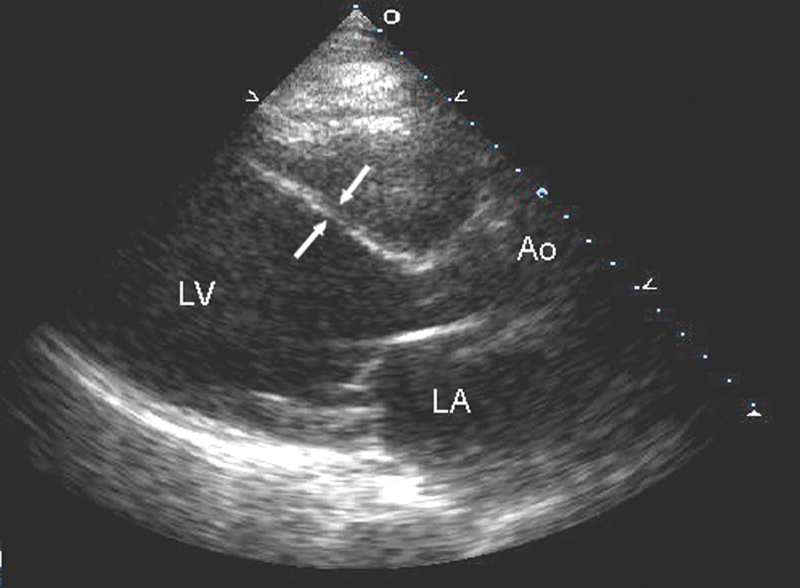

فحوصات تشخيصية لبعض امراض القلب والشرايين التاجية